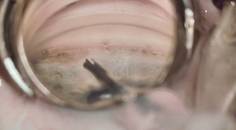

In a study on animals, citicoline preserved RGC density and improved visual acuity without affecting IOP, suggesting a neuroprotective effect.20 Early clinical trials showed that intramuscular and oral citicoline improved visual function—measured using electroretinogram, visual field, and visual evoked potentials—and slowed glaucoma progression.21,22 Studies also found that citicoline eye drops can improve optic nerve function, although they may cause more side effects than oral forms due to corneal penetrating enhancers such as benzalkonium chloride.23 Combination therapies using citicoline with other compounds such as docosahexaenoic acid and vitamin E have also shown promise.24,25